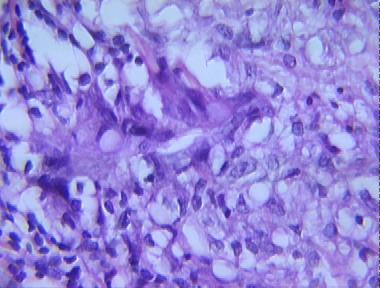

aspergillosis

Histologic Features